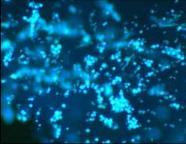

使用第 0 天

使用第 28 天

頭屑、油膩程度、頭皮狀態均有改善!

研究結果:甚至在使用後的第 1 周和長達 6 周時觀察到顯著的抗頭屑、改善泛紅和止癢作用!